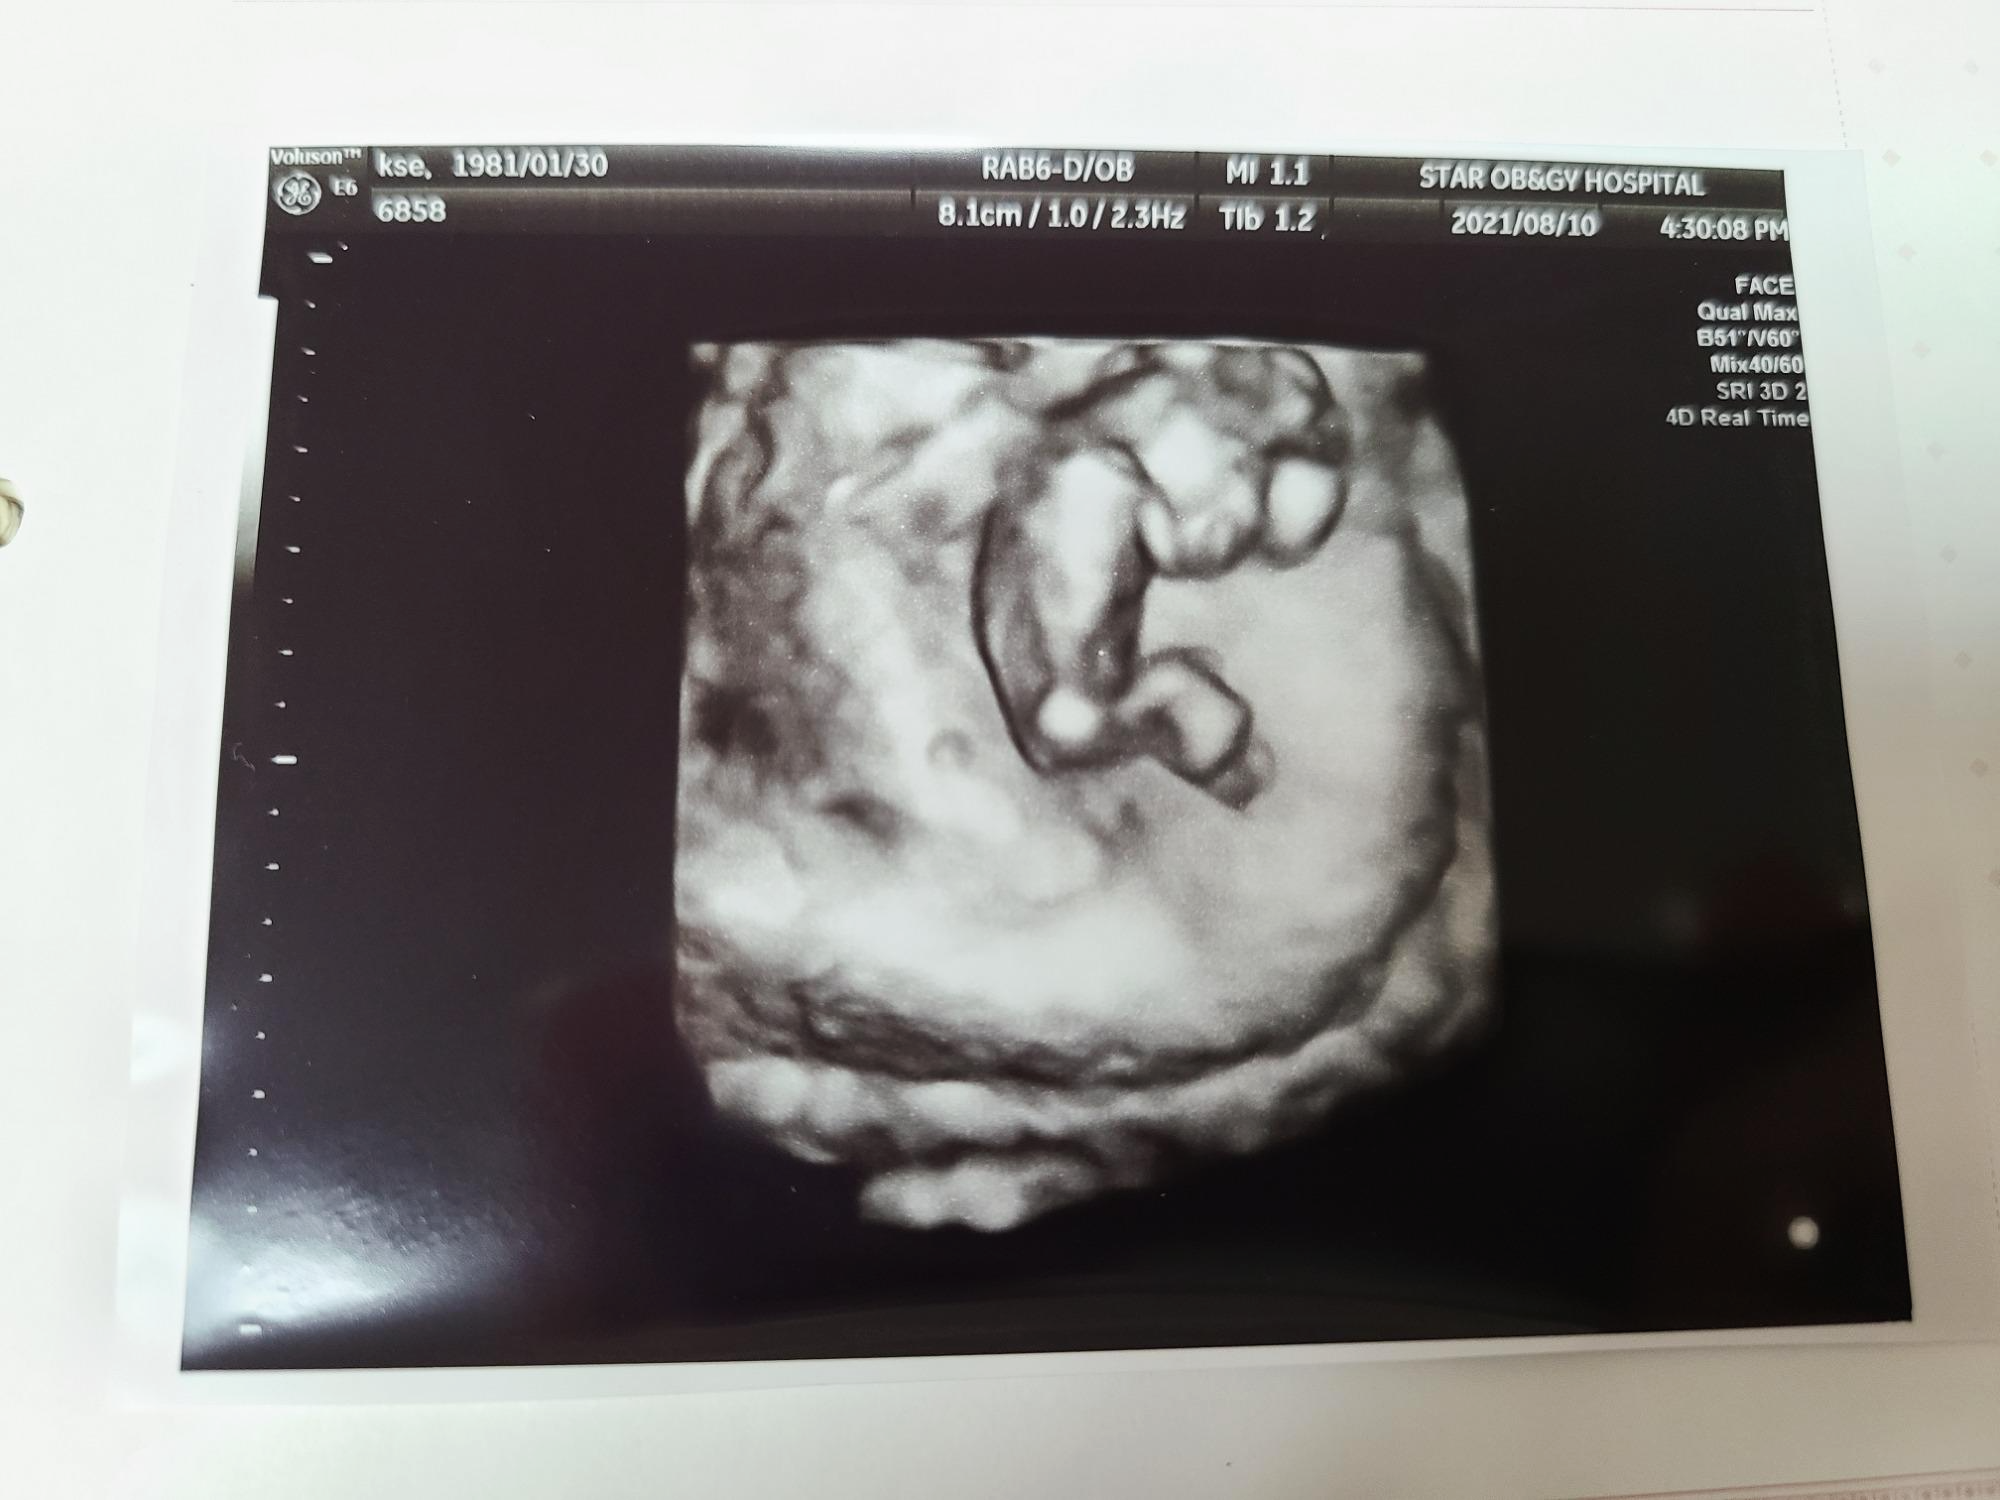

떨리는 마음으로 지난 8월 10일 12주 차에 병원에 방문해 1차 기형아 검사를 받았어요.

제가 노산이긴 하지만 담당 선생님께서 니프티 검사는 권하지 않으셨는데요, 저도 1차를 하고 혹 이상이 있다면 그때 필요에 따라 검사를 해보자고 했어요.